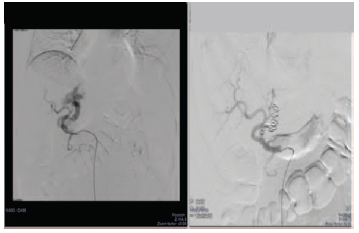

The patient underwent digital subtraction angiography (DSA), which was followed by embolization of the APF (Figure 3). After embolization, there was a gradual decrease in serum bilirubin (maximum 21 to 4.2 mg/dL) and resolution of ascites. A repeat Doppler scan of the portal venous system showed established hepatopetal flow with progressively rising portal flow velocities. The patient’s platelet count also gradually increased, and his symptoms resolved over the next 6 months.

Figure 3. Digital Subtraction Angiography Followed by Coil Embolization of Fistulous Communication Between Hepatic Artery and Portal Vein